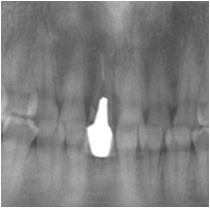

術前レントゲン写真

歯の根っこが割れているのが分かります。

インプラント埋入後のレントゲン写真